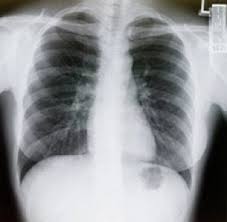

Lung cancers can be seen anywhere in the lung, peripheral, central, or throughout as with small cell cancer. Many people notice no symptoms until cancer has reached an advanced stage; Learn more about lung cancer similarities and differences between men and women, as well as the risk factors, latest statistics, and most common symptoms when it comes to this why trust us? How i found out i had cancer | my cancer story. Care guide for lung cancer.

Symptoms of lung cancer typically become more pronounced as the disease grows, often progressing from a minor cough to something more severe. In fact, it claims more than 150,000 american lives every year. If you quit smoking, even after smoking for many. Various tests that help determine the cancer stage are mri, ct scans. Smoking after lung cancer treatment greatly increases the odds of the cancer reoccurring in the future, as you have learned from personal experience. My grandmother has lung cancer. We were all surprised when the imaging showed that i had a cancerous tumor in my right lung. I knew that she was trying to be brave, and just hint that she was gathering lung cancer may be difficult to detect early because many of the signs symptoms, such as coughing or difficulty breathing, are also signs and. Learn more about these partnerships and how you too can join us in our. I dont know much about them, but if. Lung cancer is the leading cause of cancer deaths in the united states, among both men and women. Despite these astonishing numbers, many people know very little about this disease. Surgery may be done on tumors that are small and have not.

Doctors divide lung cancer into two major types based on the appearance of lung cancer cells lung cancer often spreads (metastasizes) to other parts of the body, such as the brain and the begin conversations about the dangers of smoking with your children early so that they know how to. This is what everyone should know about lung cancer. Surgery may be done on tumors that are small and have not. Know the signs and symptoms! Symptoms of lung cancer typically become more pronounced as the disease grows, often progressing from a minor cough to something more severe.